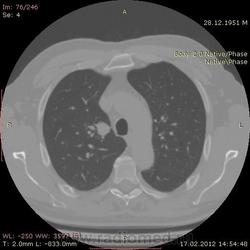

КТ.

На первый взгляд - метастазы. А так, если родственник, искать выходы на МСКТ.

Согласен с Андреем Юрьевичем - наиболее вероятно - это метастазы...исключите первичное новообразование почки.

В феврале 2012 года при очередном флюрографическом обследовании были обнаружены изменения в лёгких. По собственной инициативе было сделано КТ лёгких.

Согласен с коллегами, внешне вылитые метастазы. Но почему нет контраста? Не соли мочевой кислоты точно. Учитывая анамнез можно думать о неопроцессе почек.

Повторяюсь (мнение озвучил еще до КТ и до Ваших коментов) но это отдаленные по времени метастазы рака почки....увы....и даже если будет найден еще один первичный очаг, то все равно это - метастазы...опять - увы....